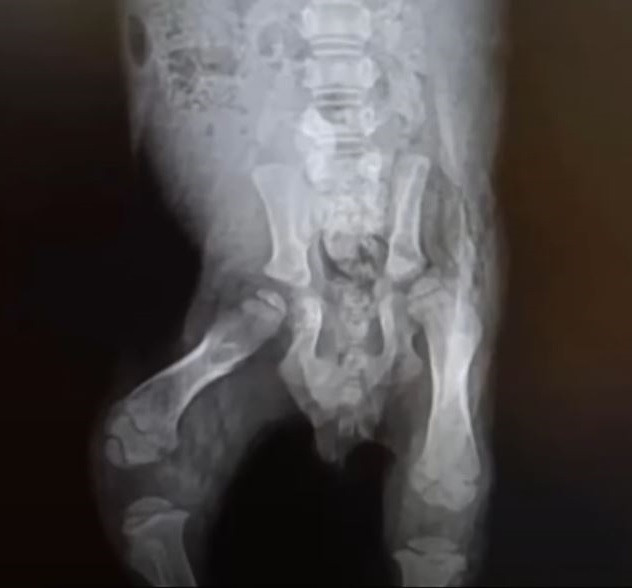

This morning was yet another example. Inside the shelter, I discovered a sick puppy, likely injured from the fall. The puppy was unable to sit, cried out in pain, and appeared to suffer from respiratory problems.

I promptly began administering fluids and antibiotics to provide relief and hydration.